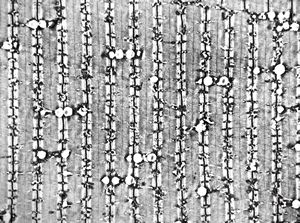

F,32y. | transversally sectioned skeletal muscle cell

mouse skeletal muscle cell - transversal section